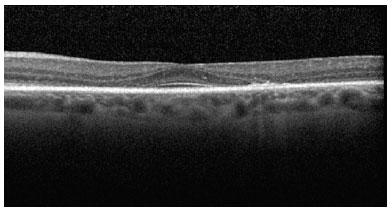

At the moderate maculopathy stage, loss of the physiological depression of the fovea occurs with interruptions of the RPE and ISOS in the parafoveal and perifoveal macular regions, characterizing the aspect in comet and macula in target. In the moderate and advanced stages, a typical fundoscopic TR lesion in the form of a bull’s eye can be identified, resulting from antimalarials. The advanced stage of maculopathy occurs with increased atrophy, foveal disruption, and visual acuity loss(15).

SD-OCT was useful for the classification of TR. Of the nine patients with TR caused by antimalarials, 44% (4) presented premacular maculopathy (Figure 1), 22% (2) at the initial stage (Figure 2), 22% (2) at the moderate stage (Figure 3), 11% (1) at the advanced stage (Figure 4), and none at the terminal stage (Table 3).